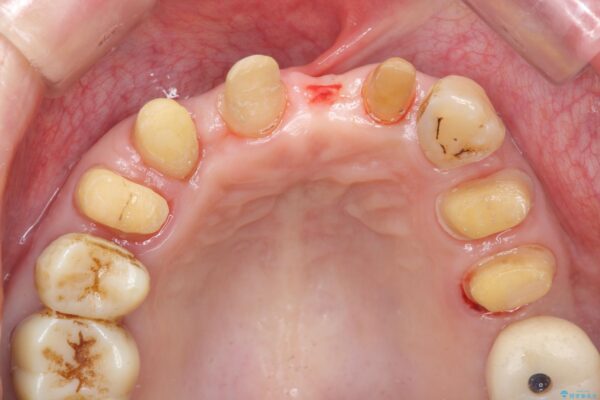

治療前

歯の総合的なマネージメントを行う包括的歯科治療の実践[ 歯周病・矯正・セラミック補綴 ] 治療前画像 歯の総合的なマネージメントを行う包括的歯科治療の実践[ 歯周病・矯正・セラミック補綴 ] 治療前画像 歯の総合的なマネージメントを行う包括的歯科治療の実践[ 歯周病・矯正・セラミック補綴 ] 治療前画像 歯の総合的なマネージメントを行う包括的歯科治療の実践[ 歯周病・矯正・セラミック補綴 ] 治療前画像 歯の総合的なマネージメントを行う包括的歯科治療の実践[ 歯周病・矯正・セラミック補綴 ] 治療前画像 歯の総合的なマネージメントを行う包括的歯科治療の実践[ 歯周病・矯正・セラミック補綴 ] 治療前画像 歯の総合的なマネージメントを行う包括的歯科治療の実践[ 歯周病・矯正・セラミック補綴 ] 治療前画像